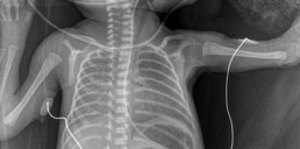

VMA offers a total of four hours of an online crash course designed for neonatal health care providers to offer a broad exposure to chest and abdomen x-rays to understand techniques, artifacts and positioning, to relate detailed pathology and interpretation of neonatal X-ray images and to differentiate between normal and abnormal findings verses artifact.